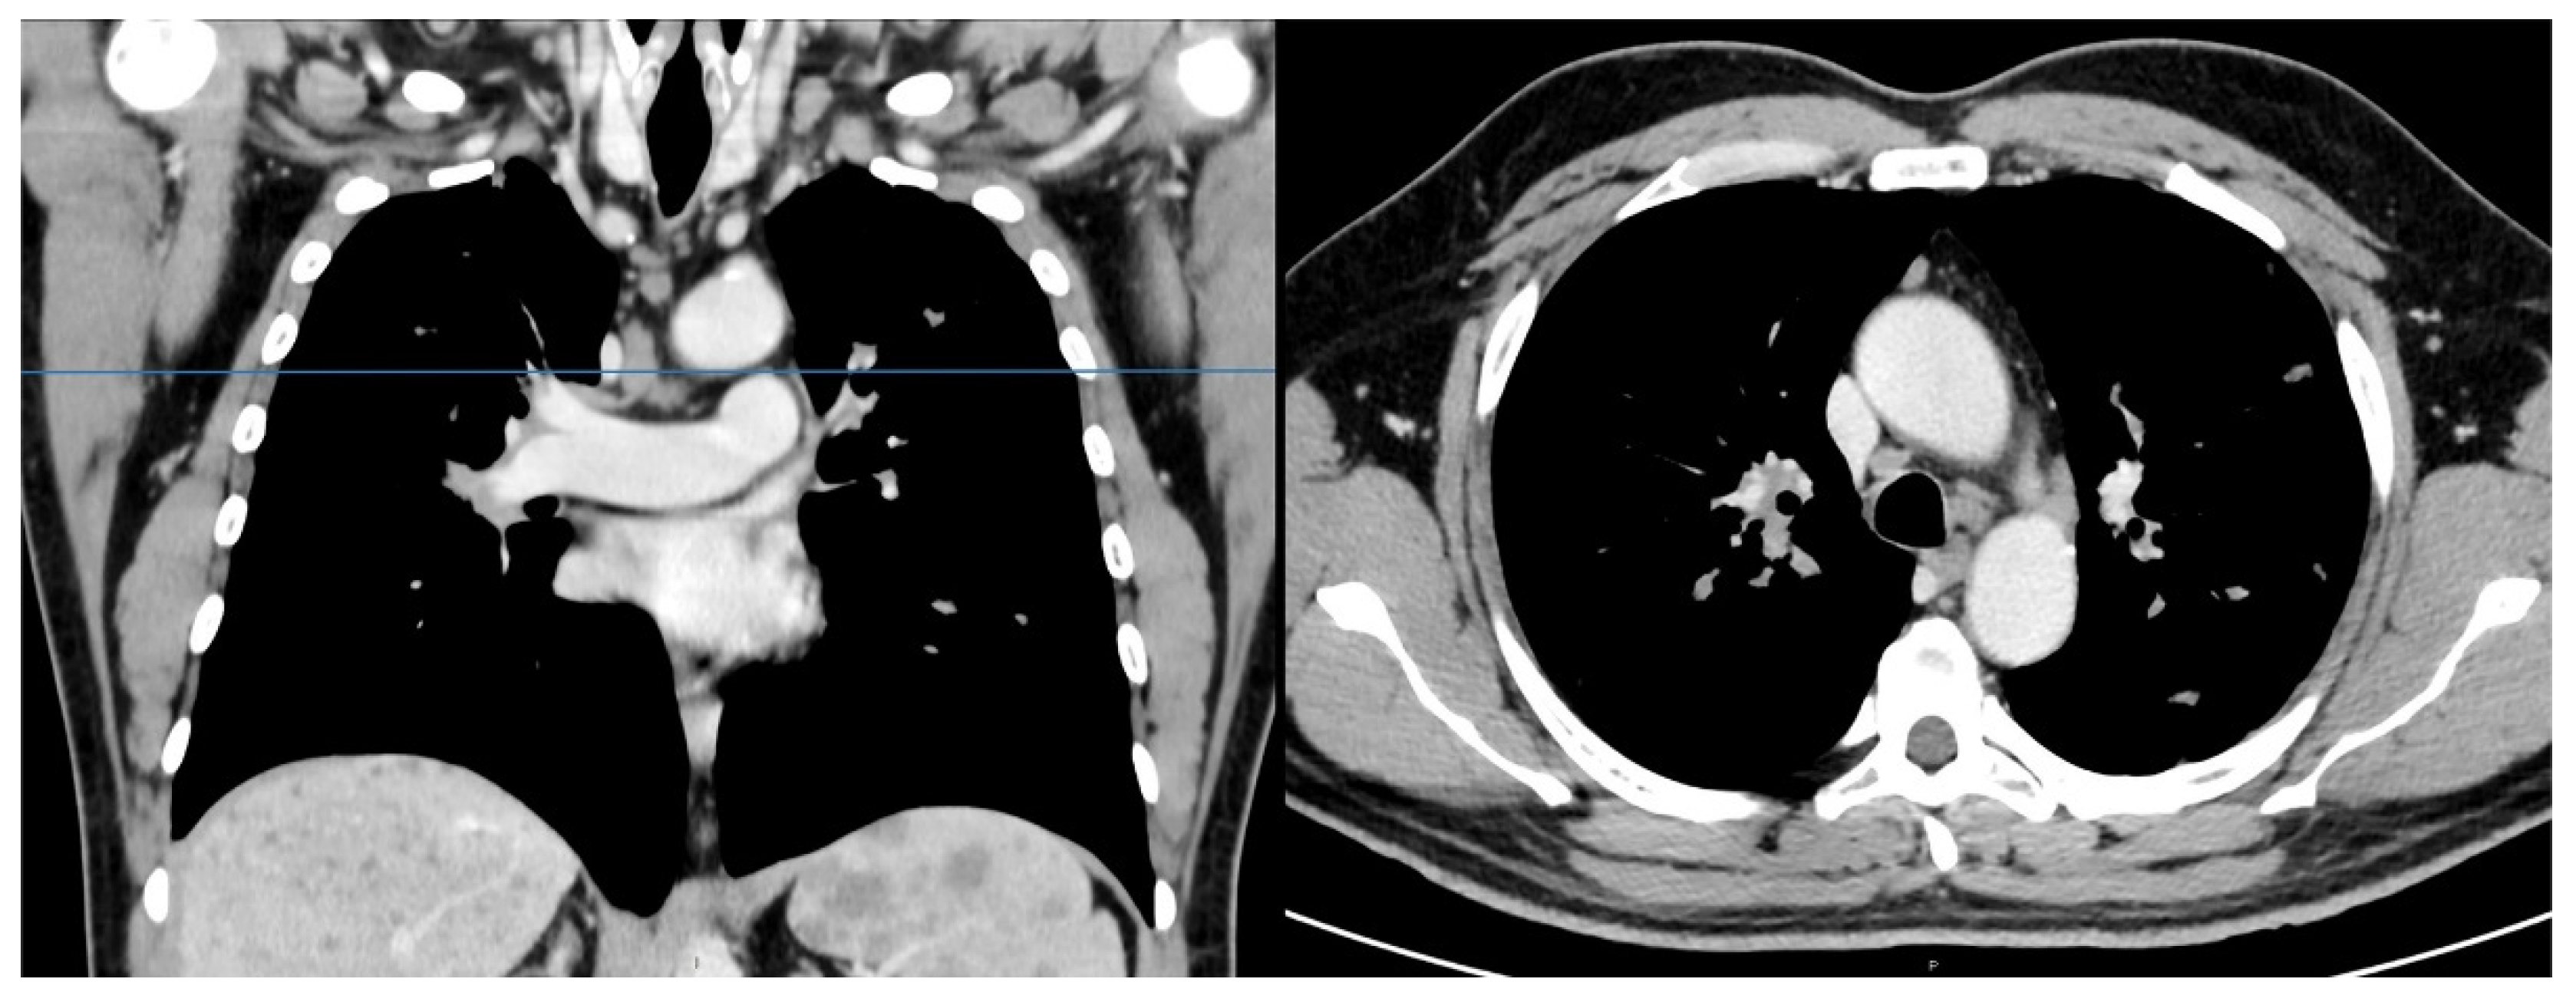

Figure 2.

Chest computed tomography showed some slightly enlarged mediastinal lymph nodes.